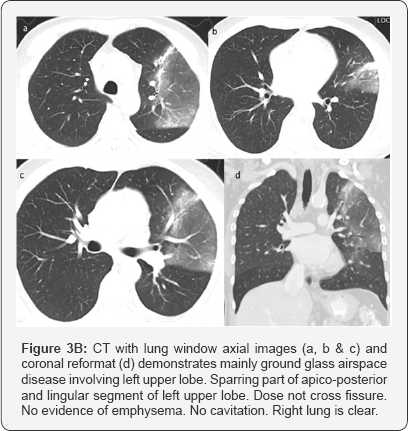

C. CT recommended to exclude underlying pathology /further evaluation considering patient age (Figure 3).

Impression: of Figure 3

CT with Contrast done after 4days of second X-ray chest.

Large area of consolidation seen involving left upper lobe with central area of ground glass opacity surrounded by rim of more density mainly at anterior aspect representing incomplete reversed halo sign.

Multiple prominent enhancing mediastinal lymph nodes. Minimal left pleural effusion. Right lung is clear.

In short term worsening and in view of history, likely community acquired pneumonia.

No mass.